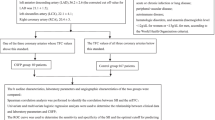

This study was carried out between November 2022 and November 2023 at Bilecik Training and Research Hospital, Şanlıurfa Mehmet Akif İnan Training and Research Hospital and Harran University Faculty of Medicine. The angiographic records of 1825 patients who underwent coronary angiography (CAG) because of the presence of ischaemia on exercise electrocardiography or myocardial perfusion sinography, unstable angina pectoris, or cardiovascular risk factors and typical anginal symptoms were retrospectively reviewed. Those who did not have a significant stenotic lesion in their coronary arteries and whose coronary artery velocity was above normal values according to the Thrombolysis in Myocardial Infarction frame count (TFC) calculation, as reported in previous studies in any of the three coronary arteries, were determined as CSFP, and those with normal coronary anatomy and normal coronary velocity were defined as normal coronary flow (NCF) [19]. Accordingly, 109 patients in the CSFP group and 105 in the NCF group, totaling 214 patients, were included in the study.

Exclusion criteria were recent acute coronary syndrome, history of coronary revascularization, severe heart valve disease, congenital heart disease, decompensated heart failure, non-sinus rhythm, malignancy, severe liver and renal failure, acute or chronic infection, pulmonary disease, autoimmune disease, hematologic disease, anemia (hemoglobin below 12 g/dL for women and 13 g/dL for men as per World Health Organization criteria), any dilatation, spasm, and dissection in coronary arteries. The study was conducted by the Helsinki Declaration and was approved by the ethics committee of Bilecik Seyh Edebali University Faculty of Medicine. Retrospective consent was waived due to this being a retrospective study.

The baseline characteristics and laboratory parameters of the patients included in the study are shown in Tables 1 and 2. Except for hyperlipidemia, both groups were similar in baseline characteristics (p > 0.05); however, the prevalence of hyperlipidemic patients was higher in the CSFP group (47.7% vs. 39.0%, p = 0.041). When comparing laboratory and angiographic findings between the two groups, patients in the CSFP group was observed to have higher levels of glucose, triglyceride, monocyte, neutrophil, NLR, PLR, SII, and TFC, while HDL-C and lymphocyte counts were lower (p < 0.05) (Table 2).

The PIV of patients in the CSFP group was observed to be higher compared to the NCF group (p < 0.001) (Fig. 1). Spearman Rho Correlation Coefficient analysis revealed a significant positive correlation between PIV and mean TFC (r = 0.518, p < 0.001) (Fig. 2).